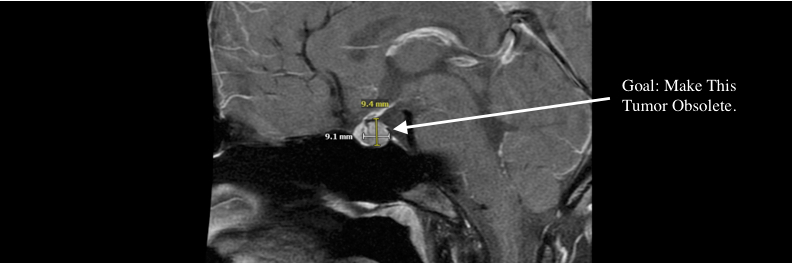

curing my partner's incurable brain tumor | ai for science VC @ side door ventures, prev biophysics research @columbia w/ stavros lomvardas, ops @pioneer labs, vc @angellist, 2x founder